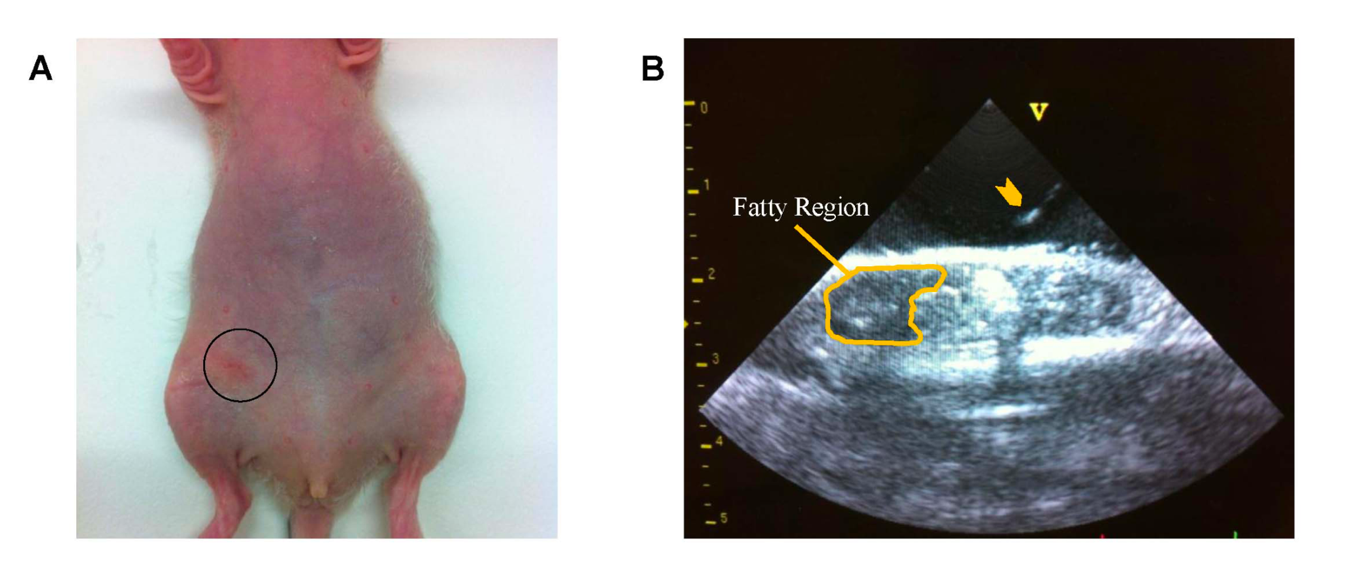

Fig. 1 Cell inoculation under ultrasound image guidance.1, 2

Fig. 2 In-vivo gadolinium contrast-enhanced magnetic resonance imaging (MRI) of orthotopic breast tumors in nude rats at 3 Tesla.1, 2